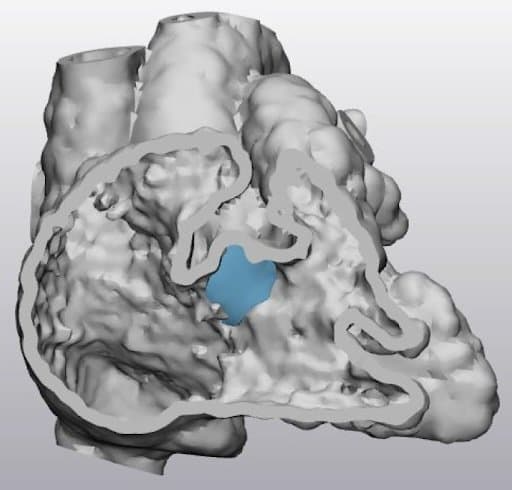

A transected digital heart model demonstrating a ventricular septal defect with a virtual patch (in blue) over the defect.

“This cross-sectional study aims to address these by involving 35 medical practitioners to subjectively evaluate VR visualization of four selected CHD cases in comparison with the corresponding 3D printed heart models (3DPHM). Six questionnaires were excluded due to incomplete sections, hence a total of 29 records (1 cardiac radiologist, 1 interventional radiologist, 3 general radiologists, 4 radiology registrars, 3 sonographers, 16 radiographers, and 1 student radiographer) were included for the analysis.”

“For 3D printing purposes, the digital heart models were converted into a standard tessellation language (STL) format. The models were printed in polyurethane ... and flexible resin (Flexible V4 Resin, Formlabs, Somerville, Massachusetts, United States), both with shore hardness of 80A."